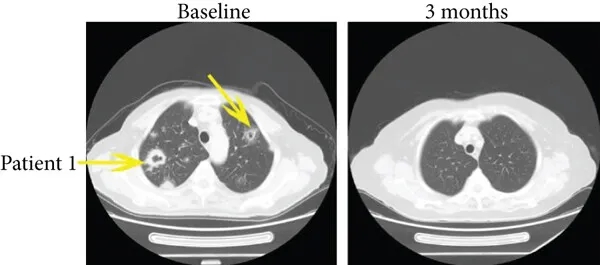

尤为值得关注的是,两例完全缓解患者的疗效更为亮眼:

病例1是一位35岁患者,治疗前伴肺转移,患者在接受免疫治疗3个月后,多发性肺转移消失(详见下图a,黄色箭头所示),PFS达15.4个月。

▲图源“J Immunol Res”,版权归原作者所有,如无意中侵犯了知识产权,请联系我们删除